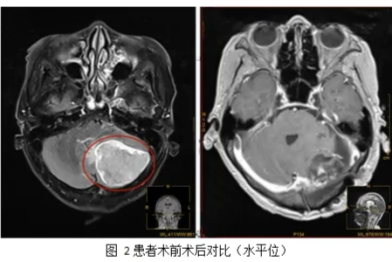

典型病例 | 18 岁的头痛谜团:当颅内与脊髓同时出现「多发肿瘤」